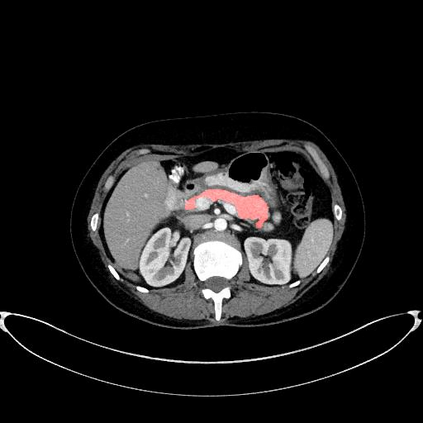

In this paper, we adopt 3D Convolutional Neural Networks to segment volumetric medical images. Although deep neural networks have been proven to be very effective on many 2D vision tasks, it is still challenging to apply them to 3D tasks due to the limited amount of annotated 3D data and limited computational resources. We propose a novel 3D-based coarse-to-fine framework to effectively and efficiently tackle these challenges. The proposed 3D-based framework outperforms the 2D counterpart to a large margin since it can leverage the rich spatial infor- mation along all three axes. We conduct experiments on two datasets which include healthy and pathological pancreases respectively, and achieve the current state-of-the-art in terms of Dice-S{\o}rensen Coefficient (DSC). On the NIH pancreas segmentation dataset, we outperform the previous best by an average of over 2%, and the worst case is improved by 7% to reach almost 70%, which indicates the reliability of our framework in clinical applications.